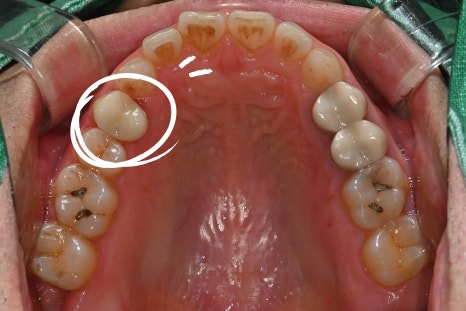

When the patient first visited the clinic

My molar cracked, and when I chew, it gives a sharp, aching pain.

After checking the photos and X-rays taken at the dental clinic,

bacteria had entered through the crack,

and the nerve was already severely damaged.